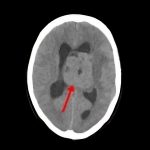

断層撮影

病名